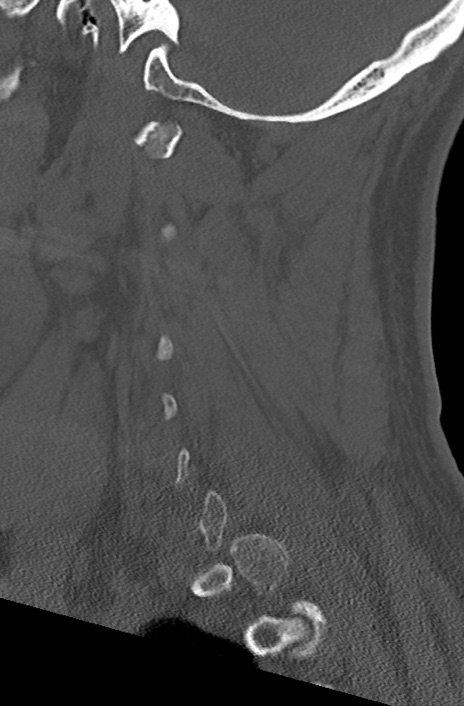

頚椎CT

冠状断像